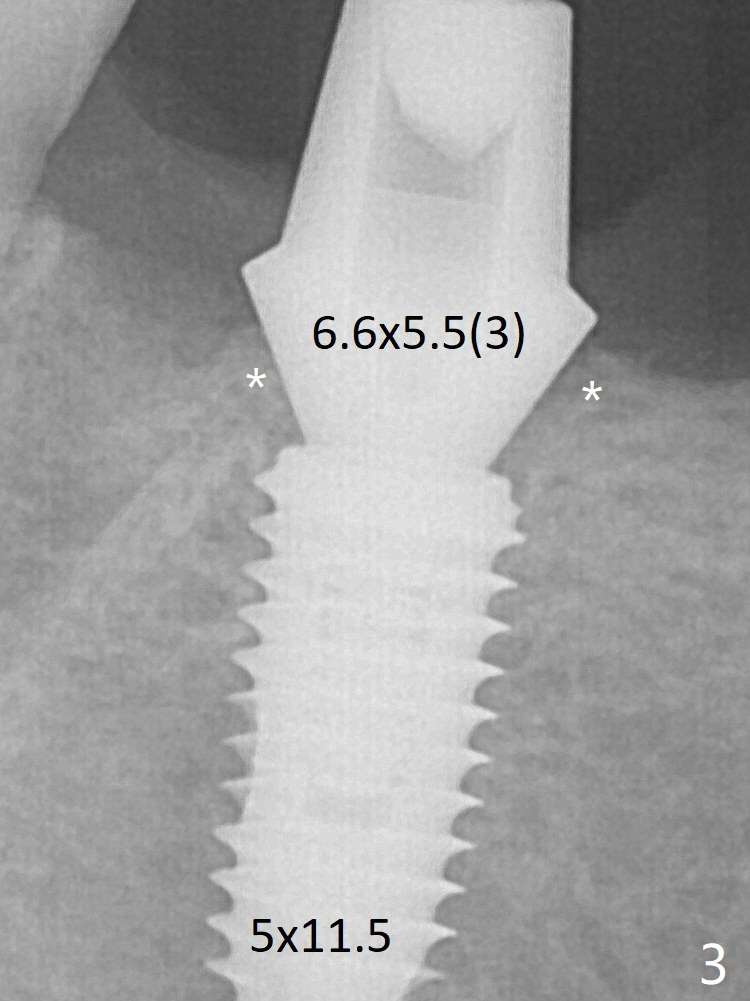

Since the Inferior Alveolar Canal is invisible (Fig.1,2 (pan should have been taken)), a 5x11.5 mm implant is placed with <20 Ncm. When a 6.5x5.5(3) mm abutment is placed, the underlying implant is turned (Fig.3).The patient returns for uncover 8 months postop; although the implant has osteointegrated apparently, the crestal bone resorbs to the implant plateau level (Fig.6 arrow). It seems that the immediate implant should be routinely placed 2-3 mm deeper.